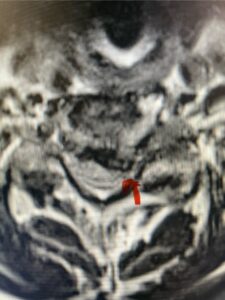

The case illustrates a more subtle finding of cervical myelopathy in a young 52 year-old male who presents with 5 months of left upper extremity weakness and burning. He also had developed over the last two months pain in his right upper extremity. He also had difficulty with fine motor skills. He had a positive Hoffman reflex and mild 4-4+ long tract weakness of his left arm and leg. Cervical MRI revealed an explanation for the patient’s symptoms (Fig. 7) as it revealed a disc osteophyte complex causing some cord flattening, slightly more to the left. We performed a C5-6 anterior cervical discectomy and interbody fusion with cage and plate (Fig. 8) He had a significant improvement in his weakness, numbness, and pain. What is interesting is that this was a relatively young patient without severe cord compression but was significantly affected by a mild amount of cord compression. This may speak to how a younger spinal cord may react much more adversely perhaps secondary to a less compliant spinal cord.

Fig. 7a Sagittal and axial T2-weighted cervical MRI’s demonstrating spinal cord compression slightly to the left secondary to disc/osteophyte complex (red arrow)